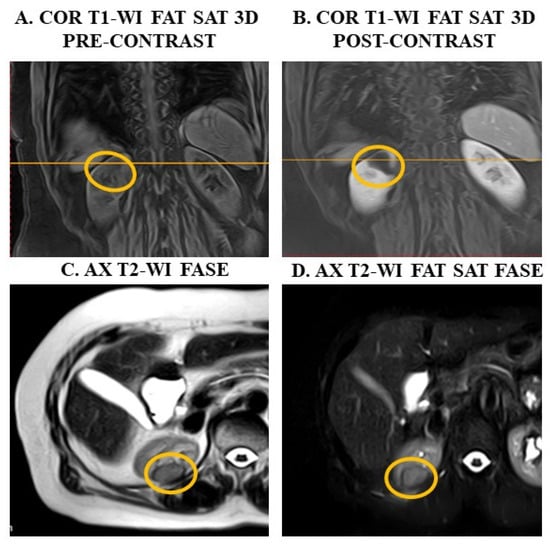

4.3. Confirm Upper Abdomen Ultrasound Diagnosis Through MRI